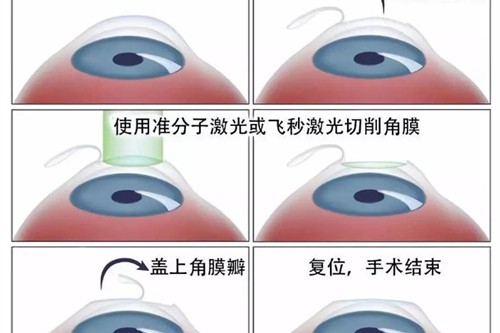

在高度近视并发症治疗方面,孙医生采用个性化方案,针对黄斑裂孔、视网膜劈裂等病变开展精密手术干预。

典型玻璃体手术包含三个关键阶段:

精细操作:在显微镜下完成视网膜前膜剥离、激光光凝等步骤

孙医生团队特别重视围手术期视觉质量评估,运用微脉冲激光等新技术更大限度保护视功能。